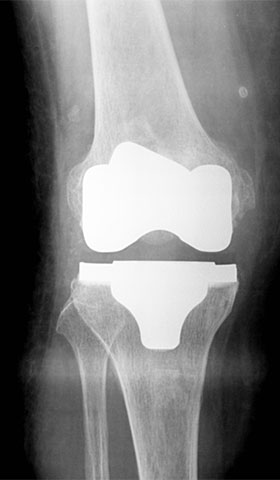

全人工膝関節置換術

深部静脈血栓予防、感染予防に充分注意を払いながら、手術直後より、関節可動域訓練、日常生活動作訓練といったリハビリを実施していきます。

手術後